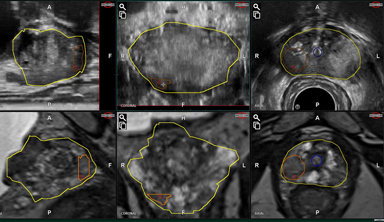

Prostate, Lesion & Urethra

3D solid model (4 windows)

3D wireframe model (1 window)